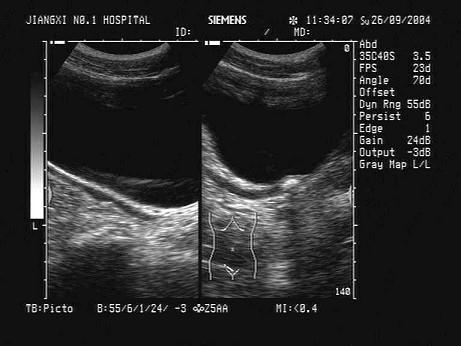

某患者右下腹痛,血尿,根据超声声像图,最可能的诊断为?(?)A.右肾结石B.右输尿管下段结石C.阑尾炎D.膀胱结石E.输尿管肿瘤

问题 某患者右下腹痛,血尿,根据超声声像图,最可能的诊断为?(?)

选项 A.右肾结石 B.右输尿管下段结石 C.阑尾炎 D.膀胱结石 E.输尿管肿瘤

答案 B